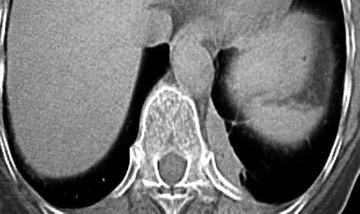

29. FALSA ELEVACIÓN DIAFRAGMÁTICA. GRASA

Ghonge NP. Hepatodiaphragmatic fat interposition' and 'increased right hemidiaphragmatic thickness': new imaging signs for early diagnosis of hepatic cirrhosis on routine CT abdomen. Abdom Radiol 2020.

Grasa simulando elevación diafragmática izquierda